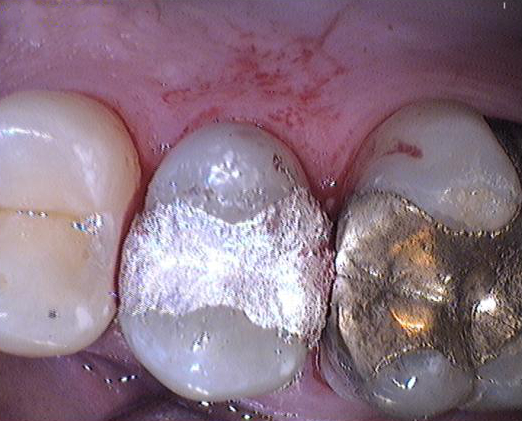

Sostituire l’otturazione sovraccarica il corpo umano, quindi l’intervento è urgente quando si verificano sintomi allergici o altri effetti collaterali summenzionati. La sostituzione comporta anche cambiamenti positivi: ci liberiamo dell'amalgama allergica e tossica, il colore dell’otturazione si adatterà al colore dei denti se viene utilizzata un’otturazione estetica.